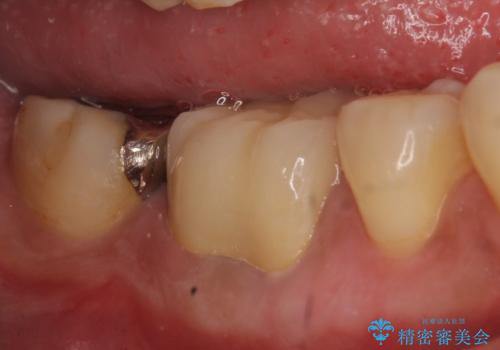

- 数年前から歯茎から膿が出る、治療してもよくならないので診て欲しいといらっしゃった方の症例です。

再根管治療を行い膿の出口の消失及び根尖病変の縮小を確認後、オールセラミッククラウンによる補綴を行いました。